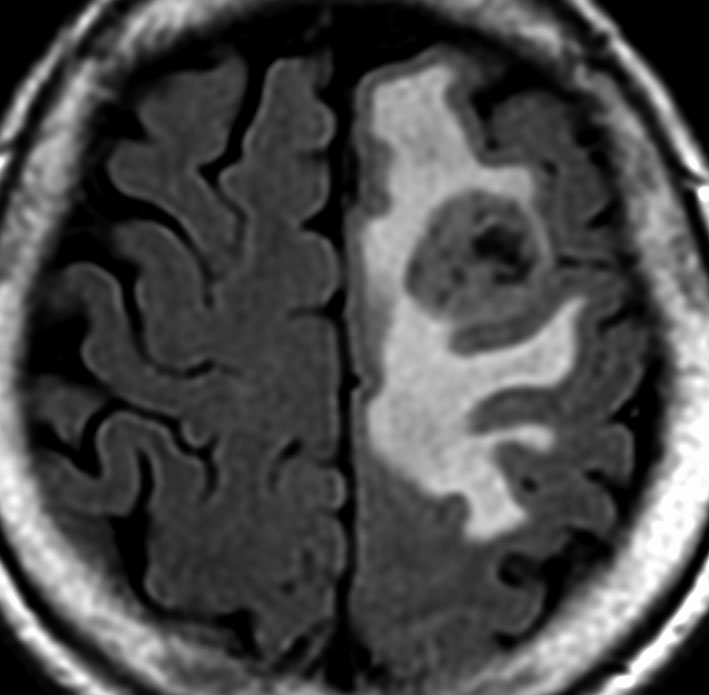

テント上 退形成性上衣腫 グレード3:EPN-ST-RELA negative

膠芽腫を思わせるような,腫瘍内部の壊死,のう胞形成,出血があります。高度の血管増生と動静脈シャントがあり,早期腫瘍静脈描出 early venous fillingがみられます。10代のおそらく右側脳室三角部辺りから発生した退形成性上衣腫です。激しい出血がありましたが全摘出 gross total removal しました。リスクをかえりみない手術も必要です。画像所見も病理組織像も超悪性腫瘍なのですが,治る可能性があるタイプです。

テント上 上衣腫 グレード2

成人に発生したものです。境界が明瞭な腫瘍で,周囲にとても強い脳浮腫があります。

組織像はグレード2,小型円形の均一な核をもち血管周囲には無核帯所見があります。EMA epitherial membrane antigenは陽性です。MIB-1染色率は非常に高く15%くらいが陽性で,再発の可能性を予想させるものでした。

グレード2で全摘出できたと考えたのですが,7年後,10年後,12年後に局所再発して,4回の開頭手術をしました。後遺症はなくて今は治って患者さんは元気でいます。テント上 上衣腫グレード2は,たとえ再発しても放射線治療を避けられる非浸潤型の例です。